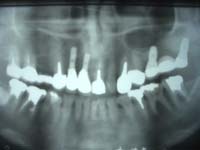

例2:60歳代女性、治療後10年経過(平成19年3月現在)

<主訴>

重度の歯槽膿漏(歯周病)。

<治療結果>

当院のインプラント治療(13本)により、主訴は消滅。現在もメンテナンスを行って頂き、問題なし。

治療途中 治療後